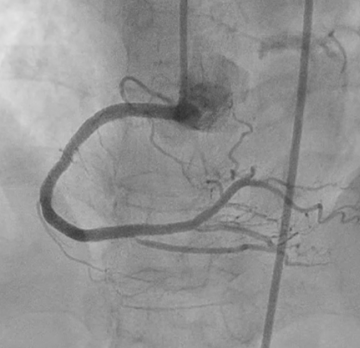

Right Coronary Angiography via right radial artery using 5 Fr TIG Optitorque demonstrated a tight lesion at mid part of Right Coronary Angiography (RCA) with heavy calcification. Left coronary angiography demonstrated non-significant stenosis at Left Anterior Descendent (LAD) and Left Circumflex (LCx) arteries. Therefore, the patient was planned to undergo PCI procedure via femoral access with IVUS guidance and preparation for rotablation.

PCI began by engaging a 7Fr JR 4.0 to the RCA ostium via right femoral artery. Wiring initially performed with Runthrough NS through Fine Cross microcatheter, but wire entered subintimal space. Several manipulations to reposition the wire were unsuccessful. Immediate contrast injection showed no flow to the distal part due to abrupt closure of the RCA Patient became angina with marked ST-segment elevation. Rewiring was immediately attempted using Fielder XT-A through Fine Cross microcatheter and the wire successfully entered true lumen A 1.5 x 1.5 mm NC balloon was placed at the lesion but balloon ruptured.A 2.0 x 15 mm NC balloon with extension catheter as support but balloon ruptured.Finally A 2.0 x 20 mm NC scoring balloon successfully inflated then flow was restored with TIMI III flow.Angina relieved, ST-segment lower and hemodynamic improvedIVUS showed massive-compressive intra mural hematoma along distal to proximal RCA with intimal tear of dissection, and the wire within false lumen at mid part RCA.Coronary fenestration attempted using 3.0 x 15 mm NC scoring balloon inflation with dual guidewire inside the lumen.Hematoma surprisingly propagated marked by contrast trapping and no flow to PLBFenestration performed again using 2.5 x 15 mm NC scoring balloon and flow successfully restored.Four DES finally decided to be deployed at distal to ostial RCAFinal angiogram showed excellent result with TIMI III flow, hematoma was disappeared with good stent apposition on IVUS examination